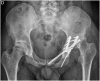

Poor prognosis factors in surgical treatment of acetabular fracture-dislocations have been well established but there is little information about how morphological abnormalities of the hip may affect the surgical outcome. Hip anatomy has a wide range of variations. Morphological abnormalities of the hip can also be observed in patients with acetabular fractures. We present a case of a complication in a patient with a complex acetabular fracture, acetabular retroversion and femoroacetabular impingement. A 31-year old male patient was transferred to our trauma center following a high speed road traffic accident. Trauma series CT revealed cerebral contusion, subdural hematoma, aortic dissection and a left transverse plus posterior wall acetabular fracture. The left hip was reduced and the acetabular fracture was treated with a Kocher Langenbeck approach in prone position. The pelvic X- ray evidenced an anatomic reduction and signs of acetabular retroversion with positive posterior wall sign and crossover sign. CT scan evidenced increased alpha angle in the femoral head neck junction. During the follow up, 2 months after the acetabular fixation, patient suffered a posterior left hip dislocation and a total cementless hip arthroplasty was performed. Patients with acetabular retroversion and femoroacetabular impingement (CAM lesion) may be at risk of posterior dislocation. The influence of acetabular version and impingement may be also closely involved in how challenging the determination of hip stability can be in patients with posterior wall acetabular fractures. Acetabular retroversion and FAI may be related to the dislocation of unstable patterns with small fragments (wall sizes less than 20%). In this case postoperative precautions were not enough. We believe capsular reattachment with anchors and bracing may be useful in these selected cases. As these patients are not candidates for retroPAO (the recommended treatment for acetabular retroversion) maybe arthroscopic anterior wall riming and CAM resection should be performed at an early stage to decrease or avoid fulcrum.